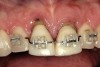

Figure 10  In these adjacent implants placed in the central and lateral positions, note the excellent interproximal bone but minimal interimplant distance.

Figure 10

Figure 11  Soft-tissue levels were acceptable at the time of placement of the final restoration.

Figure 11

Figure 12  At 6 months postinsertion, the papilla receded as bone was lost.

Figure 12

Figure 13  Twelve months after placement, soft tissue migrated apically as bone between the implants continued to resorb.

Figure 13